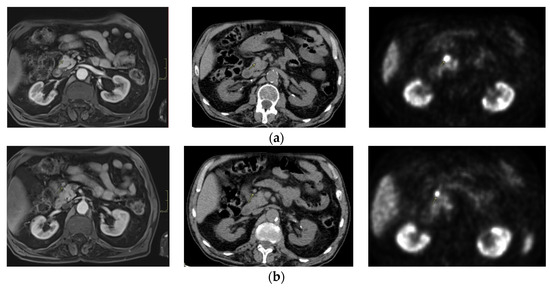

3. Second Case